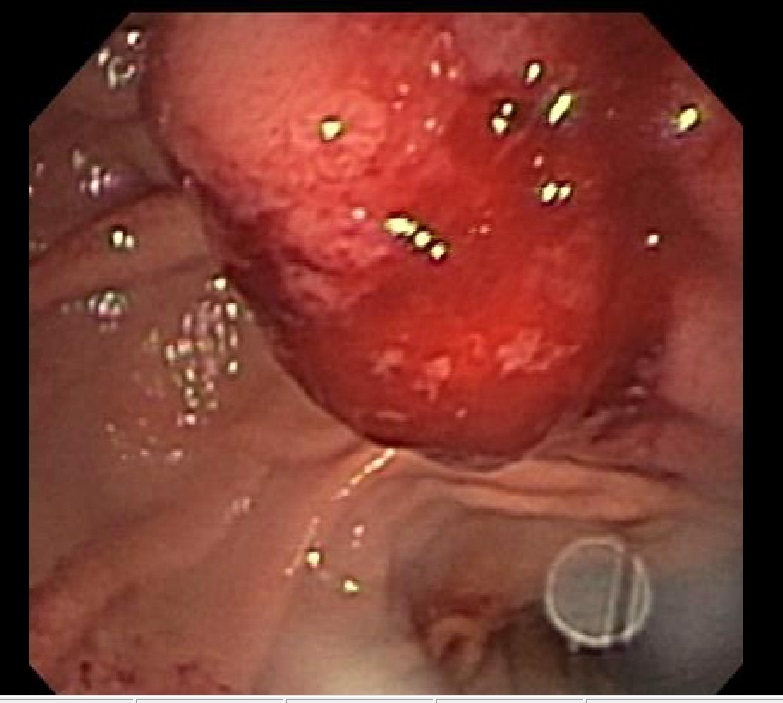

A 53-year-old man presented to the emergency department with a 2- to 3-week history of worsening upper abdominal and hypogastric abdominal pain with some radiation to his back, which was exacerbated by...